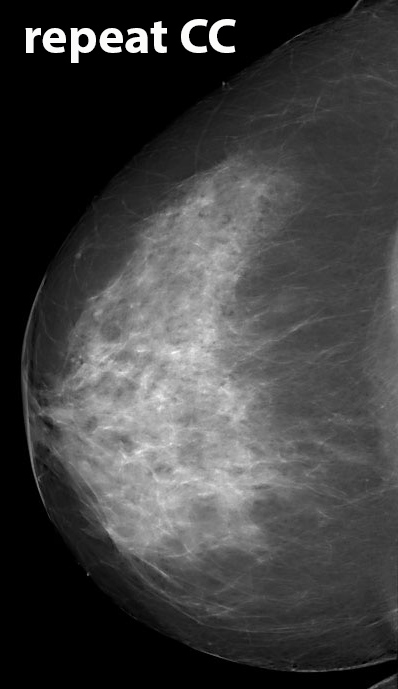

◂Breast Anatomy